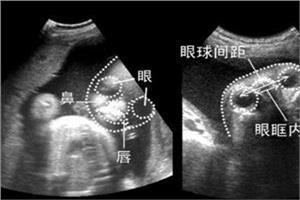

至于胎儿偏小的问题,可导致胎儿偏小的原因不仅仅是营养,还可能和实际孕周有关系。一般在产检时胎儿偏大或偏小1-2周是常见的情况。

因为产科计算孕周是从末次月经的第一天开始计算,如果着床晚,一般胎儿都会偏小。现在医生已经说胎儿其他发育正常,你可以不必过于担心,放松心情,和你的家人好好沟通,心情舒畅才能更有利于营养的吸收。